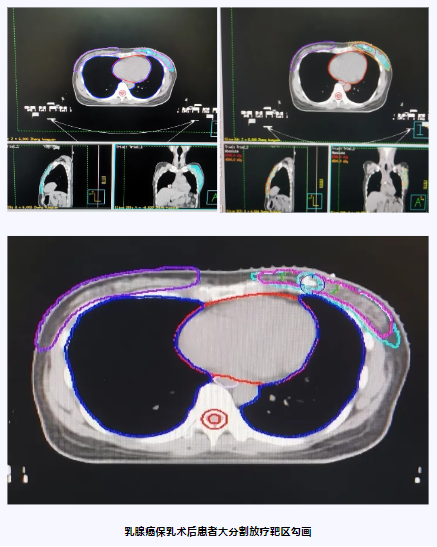

术后辅助化疗后行大分割放疗治疗乳腺癌保乳术后患者,降低局部复发率,具有可控的安全性和长期生存期。